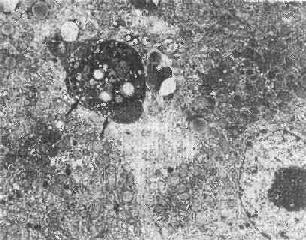

固缩坏死的最初形态表现为染色质沿皱缩的核膜下凝聚,细胞连接松解,微绒毛及细胞突起消失;细胞表面有一些泡状胞浆膨隆,可脱落形成凋落小体(图1-26),后者可见于腺腔内或被周围健康细胞所吞噬(例如肝细胞内的Councilman小体);继而内质网池扩大、断裂,线粒体结构虽仍完好,但基质呈絮状致密化。

图1-26 肝细胞凋落小体(左上)

图中左上方电子致密团块(↑),其中可见脂滴及变性崩解细胞器。

其右侧为一髓鞘样结构